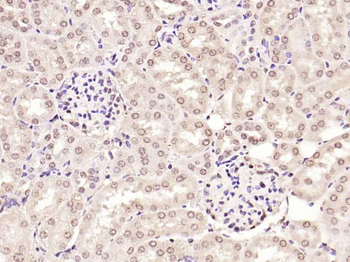

Phospho-Smad3 (Ser423 + Ser425) Rabbit Polyclonal Antibody [orb6983]

FC, IF, IHC-Fr, IHC-P, WB

Bovine, Canine, Equine, Gallus

Human, Mouse, Porcine, Rat

Rabbit

Polyclonal

Unconjugated

100 μl, 200 μl, 50 μlSMAD7 Rabbit Polyclonal Antibody [orb500819]

FC, ICC, IF, IHC-Fr, IHC-P, WB

Bovine, Porcine

Human, Mouse, Rat

Rabbit

Polyclonal

Unconjugated

100 μl, 200 μl, 50 μlPhospho-Smad3 (Ser213) Rabbit Polyclonal Antibody [orb106193]